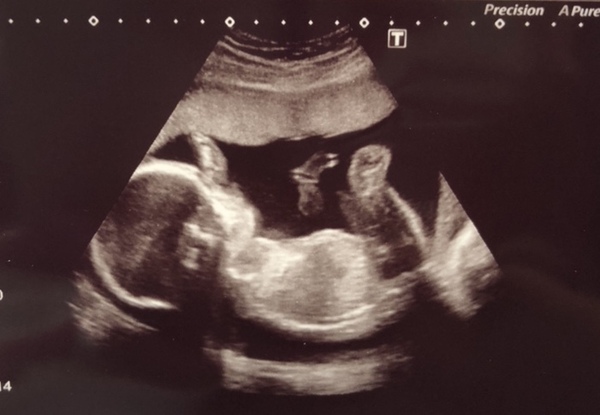

MagicalCreatures · 11/07/2018 20:39

Here’s our little man x